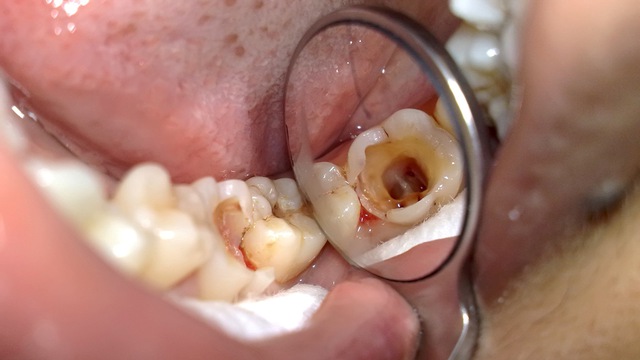

Click vào ảnh để xem 5 hình ảnh minh họa